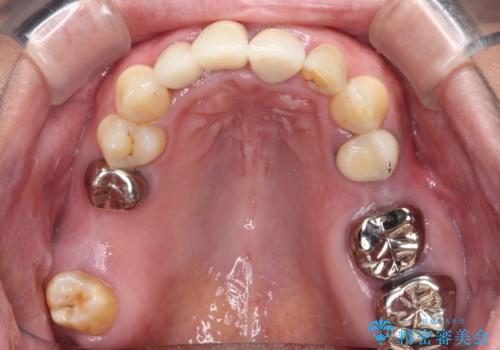

- 20年以上前に装着した前歯のメタルセラミックが不自然であることを気にして来院された患者様です。

歯肉の位置が変わり、変色した歯根が露出しているため、金属の土台をファイバーコアに交換した上で、オールセラミッククラウンにて補綴することとしました。

歯肉の位置は変更できないため、露出している歯根をクラウンで覆い隠すと歯が長く見えることを事前にお伝えしておりました。

真ん中2本は治療前よりも短めに仕上げることで、極端に長い印象を避けることができました。